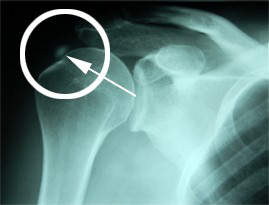

Röntgenaufnahme eines Schultergelenks:

Die Kalkablagerung an der Schulter ist deutlich als heller Fleck zu sehen.

Diese Verkalkung verursacht chronische Schmerzen, die durch eine Stosswellen-

behandlung therapiert werden können.